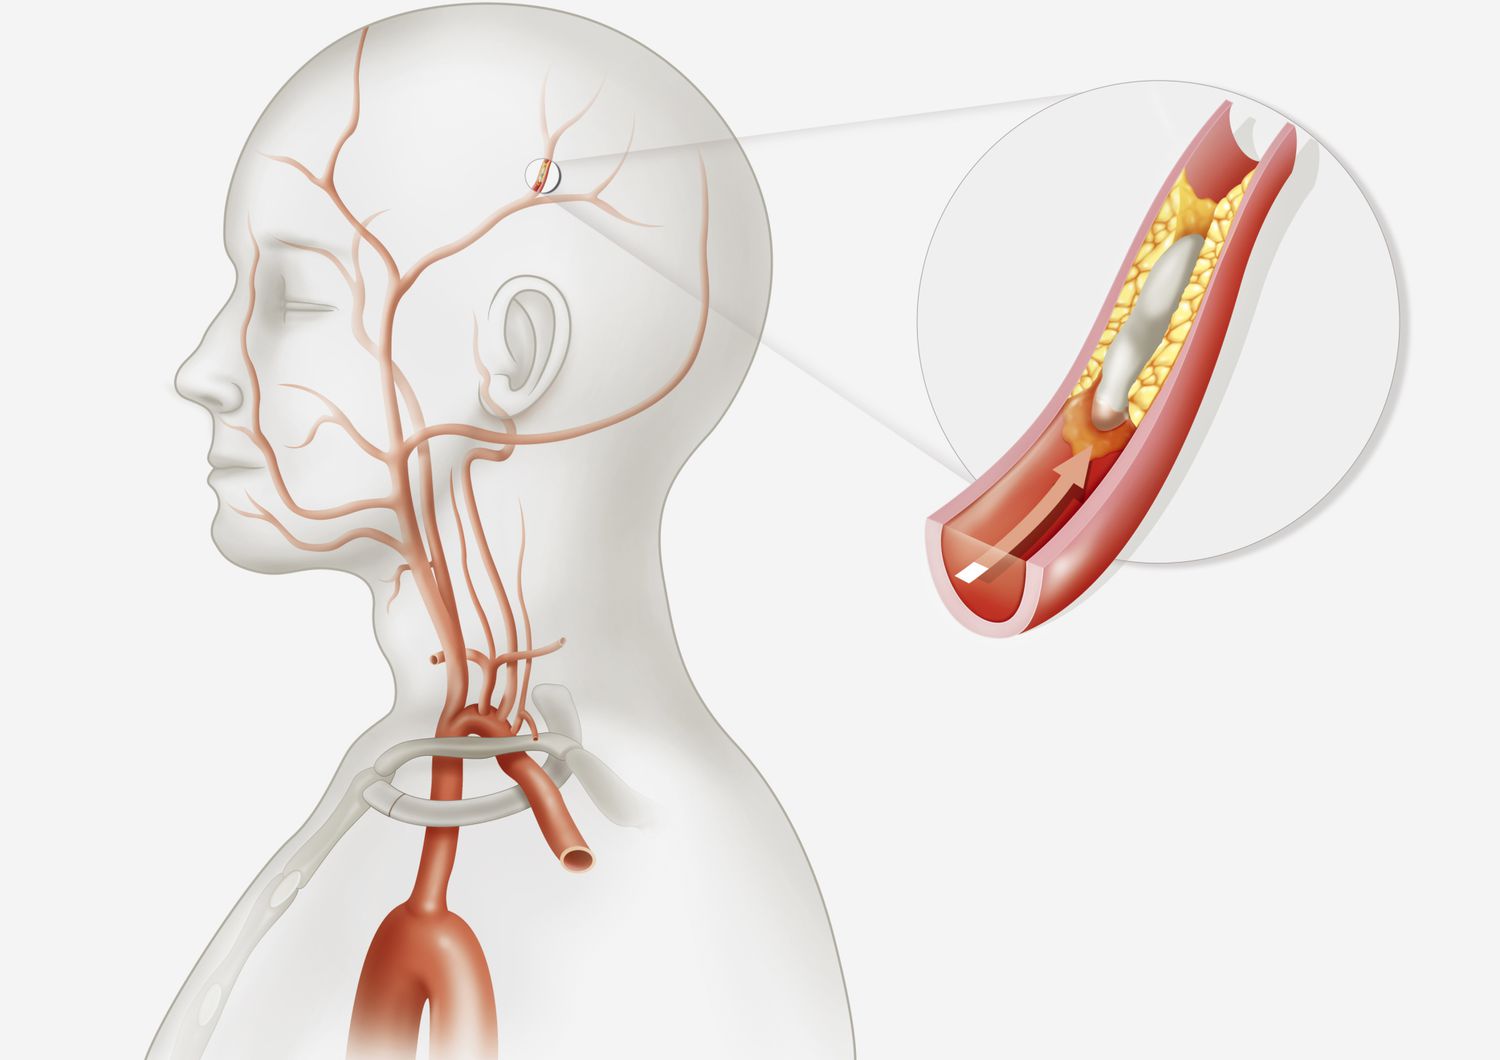

뇌졸중의 한 종류인 뇌경색은 뇌의 한 부분으로의 혈류 장애로 인해 뇌 조직이 손상되어 발생하는 의학적 응급 상황입니다. 뇌경색 초기증상 및 징후를 빨리 인식하는 것은 즉각적인 치료로 사망의 위험을 크게 줄일 수 있기 때문에 아주 중요합니다. 이 글에서는 뇌경색 초기증상, 뇌경색 및 뇌졸중 치료에 대한 미국 의학 협회(AMA) 지침, 추가정보에 대해 알아보려고 합니다.

• 허혈성 뇌졸중(혈전이 뇌로 가는 혈류를 차단하여 발생)의 경우 증상이 시작된 후 처음 4.5시간 이내에 조직 플라스미노겐 활성화제(tPA)와 같은 혈전 용해 약물을 투여하면 결과를 크게 개선할 수 있습니다. 경우에 따라 기계적 혈전 제거술과 같은 혈관 내 절차를 수행하여 혈전을 제거하고 혈류를 회복할 수도 있습니다.